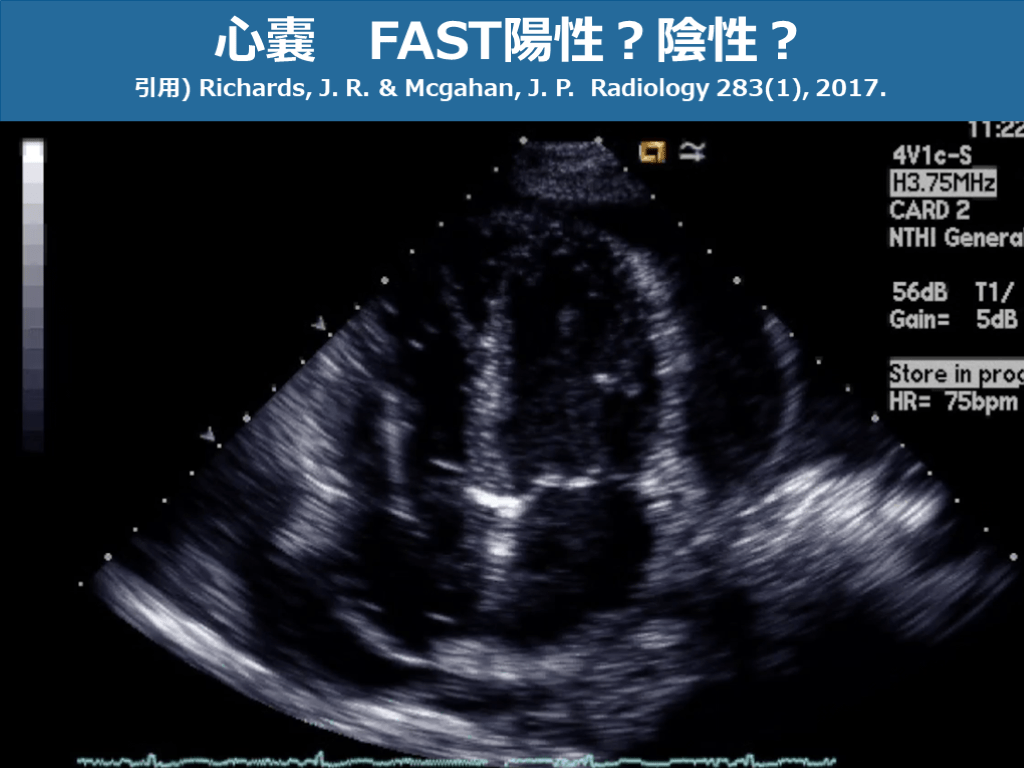

心嚢 FAST陽性?陰性? 引用) Richards, J. R. & Mcgahan, J. P. Radiology 283(1), 2017. スライド画像)広島大学病院 演者作成

心嚢 FAST陽性?陰性? 引用) Richards, J. R. & Mcgahan, J. P. Radiology 283(1), 2017. スライド画像)広島大学病院 演者作成 心尖部周囲に少量の心のう水貯留あり